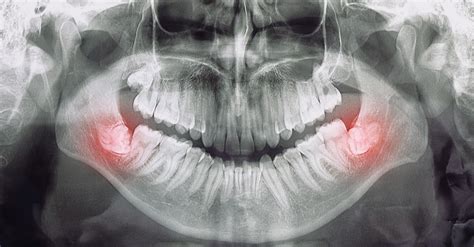

Cuando las muelas del juicio no logran erupcionar completamente o lo hacen de forma parcial y en una posición inadecuada, se les denomina “muelas del juicio impactadas” o “incluidas”. Es importante mencionar que no todas las personas desarrollan las cuatro muelas del juicio, y en algunos casos, es posible que no aparezcan en absoluto.

- Impactación: dado que son las últimas piezas dentales en salir, es frecuente que las muelas del juicio no puedan erupcionar completamente debido a la falta de espacio en la boca. Además, en muchos casos, la muela del juicio se encuentra en una posición que dificulta su salida. En consecuencia, esta pieza dental se puede quedar “atrapada” dentro del hueso, bajo la encía.

- Que no tengan espacio para salir, quedando atrapadas dentro del hueso maxilar - en este caso, se habla de «muelas incluidas», a las que hay que ir estudiando su posición y sus posibles complicaciones a lo largo del tiempo. En los dos últimos casos, las muelas pueden comenzar a “empujar” en cualquier momento para intentar erupcionar, lo que puede producir dolores en la zona.